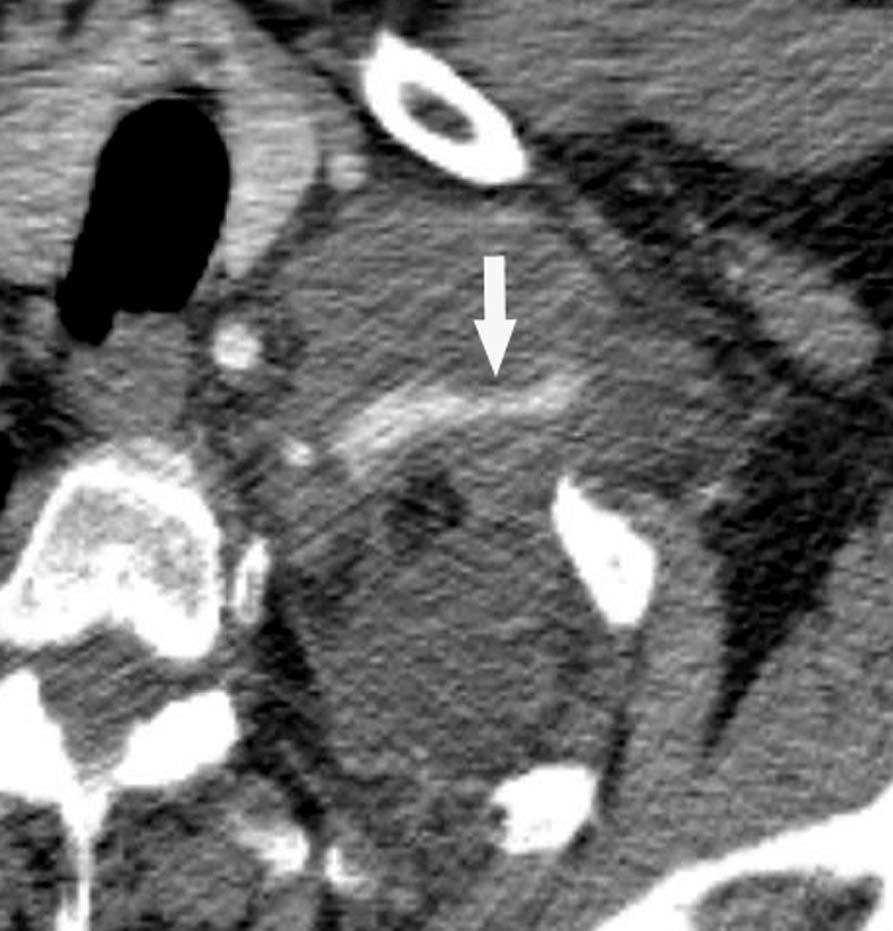

Fig. 4.--Invasión vascular. Tomografía computarizada (TC) torácica con contraste. Corte axial (A) y reconstrucción coronal oblicua (B). Invasión tumoral por continuidad de la vena pulmonar inferior (flecha).

Pese a las conocidas limitaciones de la TC, ésta continúa siendo la técnica de elección en la estadificación del tumor en los pacientes con CPNM; su sensibilidad y especificidad en la determinación de la infiltración de pared oscilan entre el 38 y el 87% y del 40 al 90%, respectivamente, según las series. El desarrollo de nuevos equipos de TC helicoidal y principalmente las TC multidetectoras (TCMD) proporcionan unas imágenes 2D de mayor resolución con la posibilidad de hacer reconstrucciones multiplanares (MPR) en distintos planos del espacio e incluso 3D con la consiguiente mejora de la valoración del tumor, su extensión e infiltración de estructuras vecinas5 (fig. 4). Así, con la TCMD se puede poner de manifiesto con mayor fiabilidad la invasión de la cisura, la pared torácica o el mediastino, y además es capaz de determinar, gracias a las reconstrucciones de volumen, la relación exacta del tumor con la vía aérea (fig. 5). El progreso en la capacidad diagnóstica deriva del incremento en la resolución de las imágenes obtenidas y de la posibilidad de emplear nuevas aplicaciones como la broncoscopia virtual y la visualización en tiempo real. La broncoscopia virtual es útil para valorar la invasión del árbol traqueobronquial con la finalidad de planificar la cirugía, también como guía para el fibrobroncoscopista y, por último, porque permite ver el árbol bronquial distal a la estenosis (fig. 6)6. La capacidad de ver la imagen en tiempo real es especialmente útil cuando se emplea como guía en maniobras intervencionistas como biopsias percutáneas, ya sea con finalidad diagnóstica o como parte de la estadificación (fig. 7). Esta técnica de guía de biopsia denominada TC fluoroscopia reduce el número de pases y el tiempo global de la exploración, implica un menor riesgo de lesión de estructuras y permite la visualización inmediata de las posibles complicaciones7.